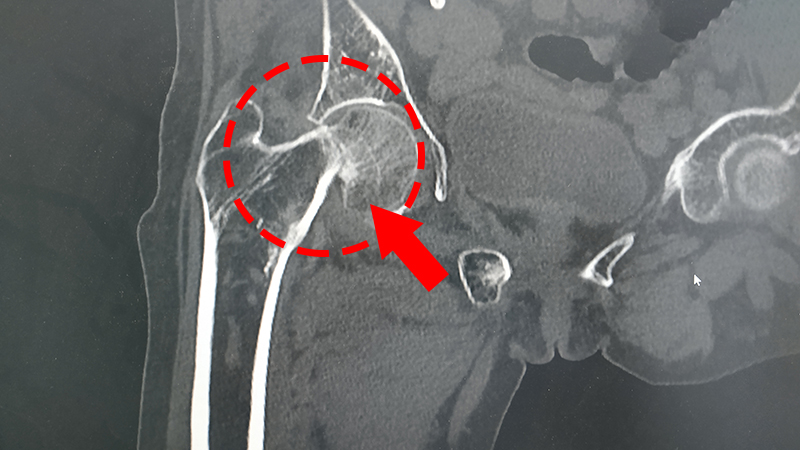

医师通过骨盆X片见:吴婆婆右股骨颈骨折,骨折端移位明显,诊断为“右股骨颈骨折”。

之后在我院进行了“右侧人工股骨头置换术”,手术非常顺利,术后髋关节也比较稳定,髋关节高度及各角度测量良好,假体活动自如,后在崔医生以及骨一科全体医护人员的精心照料下康复出院啦。